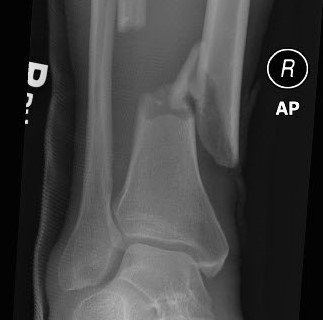

For more than a hundred years, surgeons have known that open fractures (in which the bone protrudes from the skin) heal better if dead and damaged tissue is removed. However, there has been intense debate about how best to do this.

Now, a large international clinical trial published in the New England Journal of Medicine has finally laid this debate to rest. The trial compared two different salt solutions commonly used to flush out the wounded area and three different flushing pressures. Results show that flushing pressure made no difference, but patients who received a salt solution with soap were 32 percent more likely to require another operation than patients who received a plain salt solution.